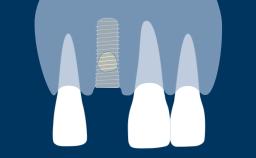

Um pré-requisito para o sucesso do tratamento com implantes é que o implante seja instalado com estabilidade primária e se integre com sucesso ao osso da arcada em uma posição predeterminada, direcionada pela prótese. Para a osseointegração do implante, é essencial que o osso vivo seja tratado com cuidado durante o procedimento de instalação do implante. Os clínicos, portanto, precisam entender a composição e a natureza do osso vivo antes de realizar procedimentos com implantes dentários.

Diante do requisito de se instalar implantes na posição correta determinada pelo planejamento protético prévio geralmente significa que há falta de volume ósseo para incorporar completamente o implante. Implantes que não são completamente cobertos por osso podem apresentar risco em uma variedade de complicações, incluindo recessão de tecidos moles, inflamação e infecção devido à colonização da superfície do implante exposto à biofilmes bacterianos e até a perda do implante devido ao suporte ósseo insuficiente. Procedimentos de enxerto para aumentar o volume do osso são frequentemente necessários para garantir que os implantes estejam completamente cobertos de osso. Este módulo descreverá a composição e a natureza do osso vivo, materiais de enxertia utilizados na implantodontia, bem como diferentes modos de cicatrização de diferentes enxertos.